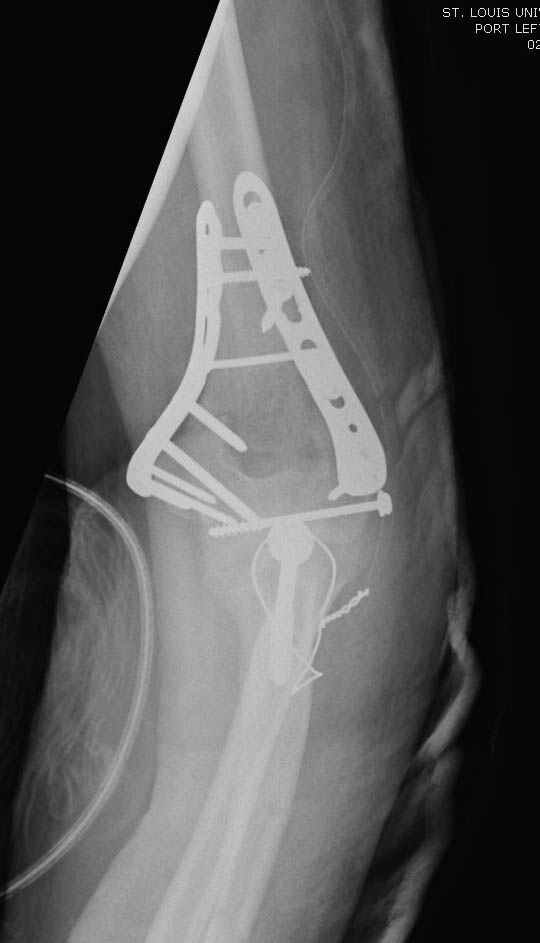

Примерный случай, только перелом был открытый, в задне-медиальной стороне рана около 2 см по характеру "изнутри кнаружи", неврологический статус со слабостью сгибания мизинца, также слабая абдукция и аддукция указательного пальца и сгибания в кисти.

Больному сделали обработку и наложили временный аппарат внешной фиксации плечо-предплечье.

На шестой день сделали открытую репозицию чрезлоктевым доступом двумя locking plate, локтевой нерв был ушибленным, после операции положительная динамика в Flexor Carpi Ulnaris. Фиксацию локтевого отростка произвели tension band technique с дополнительным шурупом.

Этапы операции на снимках....